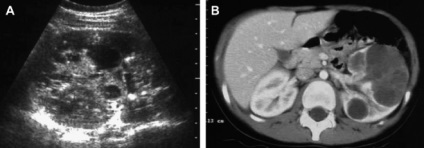

Caracteristici ale structurii și dispunerea rinichi organe pereche determină un diagnostic complex de posibile anomalii. Identificați formarea străine care se pot dezvolta pe parcursul vieții sau din cauza anumitor boli și, în caz de rinichi este dificil - din cauza faptului că rinichii sunt situate în spatele cavitatea abdominală. chist parenchimul renal este, de asemenea, practic imposibil de observat, inclusiv în SUA, atâta timp cât tumora nu se extinde până la o anumită dimensiune. chist parenchimul renal lăsat ce este și modul în care aceasta diferă de la o tumoare pe partea dreaptă? Această întrebare este de interes pentru mulți dintre cititorii noștri, iar apoi vom raspunde la ea cu toate detaliile.

În identificarea cele mai mici simptome ale bolii, precum și semne de probleme cu sistemul genito-urinar, pacientul trebuie să consulte imediat medicul dumneavoastră. Medicul va aloca control necesar, scanarea cu ultrasunete a cavității abdominale și de a determina chisturi optime de tratament parenchimului rinichi dreapta sau organism din partea stanga.